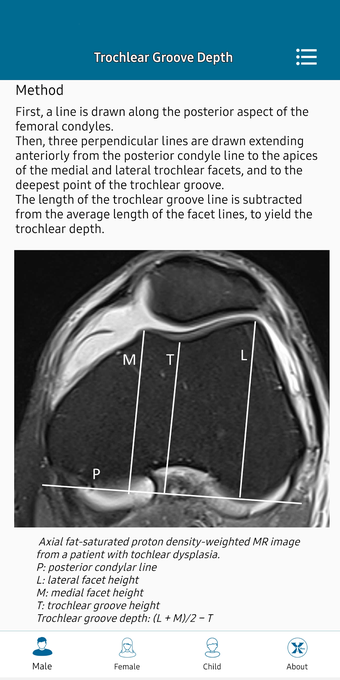

This helpful app is intended for all those who practice medical imaging and for the radiologists who use the application in their work. It is an atlas of the main measurements in radiology and their normal values, divided into six subspecialties: osteoarticular, cervical region, thorax, cardiovascular, abdomen, and pelvis.

The lessons are organized in a way that allows for easy and fast access to the information. In addition, the application has a section with a summary of the main points of the sub-specialties, which can help the user quickly grasp the meaning of the measurements and the importance of each of them.